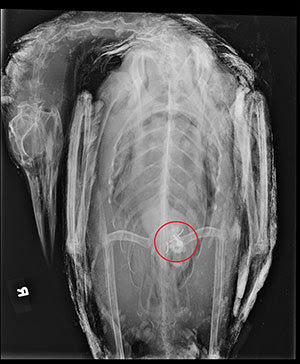

A radiograph reveals a lead tackle object in the gizzard of the deceased loon. Photo courtesy of Meadow Pond Animal Hospital.

MOULTONBOROUGH, N.H. – The first documented lead-poisoned loon collected from New Hampshire waters this year was discovered July 1, 2015, on Lake Winnipesaukee. The loon was collected in Loon Cove of Alton Bay, after it was found dead on the beach. Radiographs at Meadow Pond Animal Hospital showed a lead tackle object in the loon’s gizzard, so it was transported to UNH Diagnostic Veterinary Laboratory to be necropsied. Necropsy results found a lead jig and blood tests revealed toxic blood lead levels. July and August are when lead-poisoned loons are most often found. This correlates with peak lake use and fishing pressure in the state.